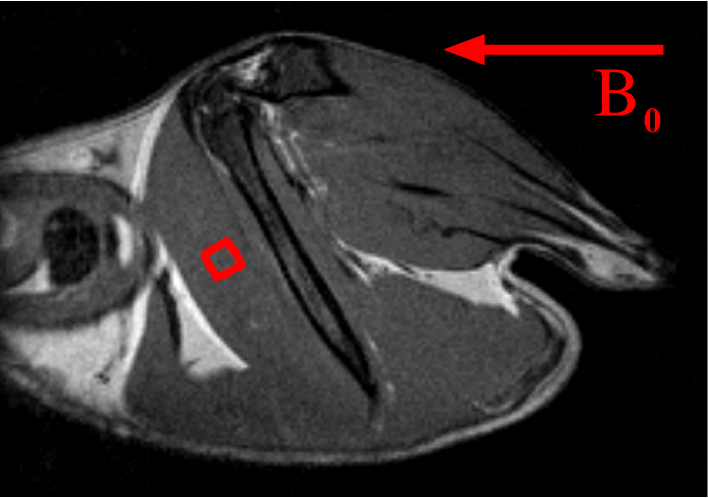

Zur Gewinnung eines Einblicks in die Untersuchungstechnik der Magnetresonanztomographie ist es sinnvoll, die grundlegenden Mechanismen zu rekapitulieren. Während der magnetresonanztomographischen Untersuchung des Herzens befindet sich das Myokard in einem starken äußeren Magnetfeld mit der Flussdichte B0subscript𝐵0B_{0}. Durch Anlegen von Magnetfeldgradienten und Einstrahlen von Hochfrequenzpulsen können aus den MR-Signalen Bilder des Myokards gewonnen werden. Zur Entstehung des MR-Signals tragen die Protonen der Wassermoleküle bei, die sich in den Herzmuskelzellen und im Interstitium des Myokards befinden. Wie in der Abb. 1 dargestellt ist, besteht das Myokard aus Muskelzellen, die von Kapillaren versorgt werden.

Refer to caption

Abbildung 1: Faserarchitektur des Myokards. Die blutgefüllten Kapillaren (blau) sind gegenüber dem äußeren Magnetfeld in z𝑧z-Richtung um den Winkel θ𝜃\theta geneigt (modifiziert nach [3]).